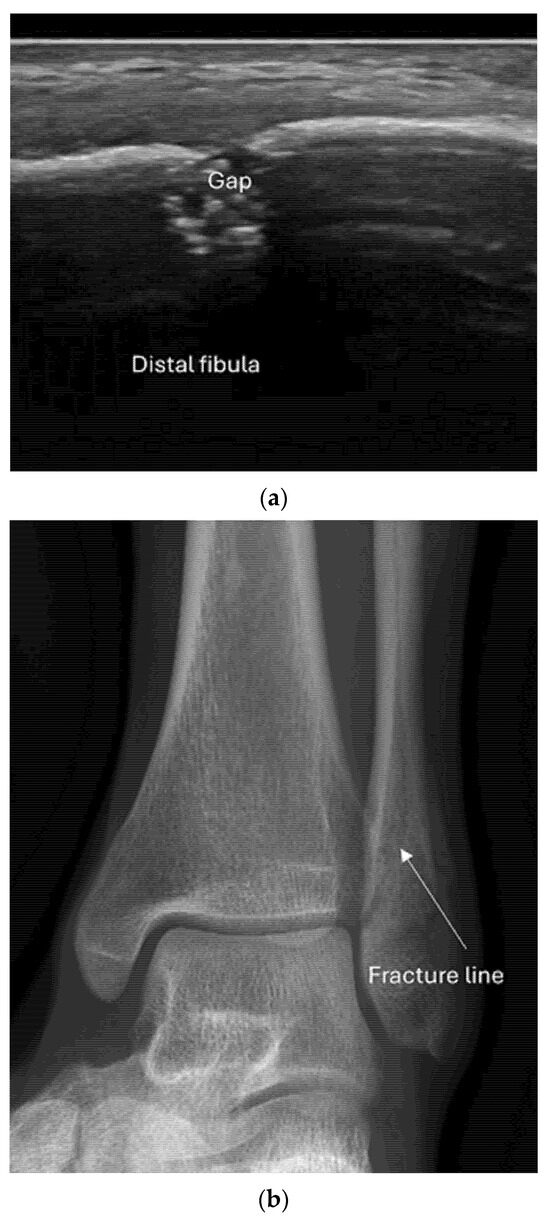

4.2. Sonoanatomy of Fractures [Figure 5, Figure 6, Figure 7 and Figure 8]

- Irregularity, interruption, or gaps in the cortical line: the cortical bone normally appears as a continuous, bright echogenic line, which is interrupted or irregular in the presence of a fracture.

- Reverberation artifacts within or adjacent to the fracture gap (also known as the “chimney sign”): these repetitive echoes are caused by ultrasound waves reflecting off the fracture surfaces.

- Bulging or abnormal angulation of the cortical layer: deformities or outpouchings of the normally straight cortical surface indicate displacement or bending at the fracture site.

- Osseous avulsions and small bone fragments: detached bone pieces that appear as discrete, hyperechoic fragments adjacent to the main bone.

8.2. Screening of Patients with Suspicion of Occult and Stress Fractures (Figure 11 and Figure 12)

- Recommendation 2: Given the promising but limited evidence, ultrasound should be considered a first-line imaging tool for suspected occult fractures, except in the pelvis and vertebral column.

- Recommendation 3: Ultrasound should be used as first-line imaging for suspected stress fractures, with follow-up X-ray if evidence of a stress fracture is identified. Exceptions include pelvic and vertebral column fractures.